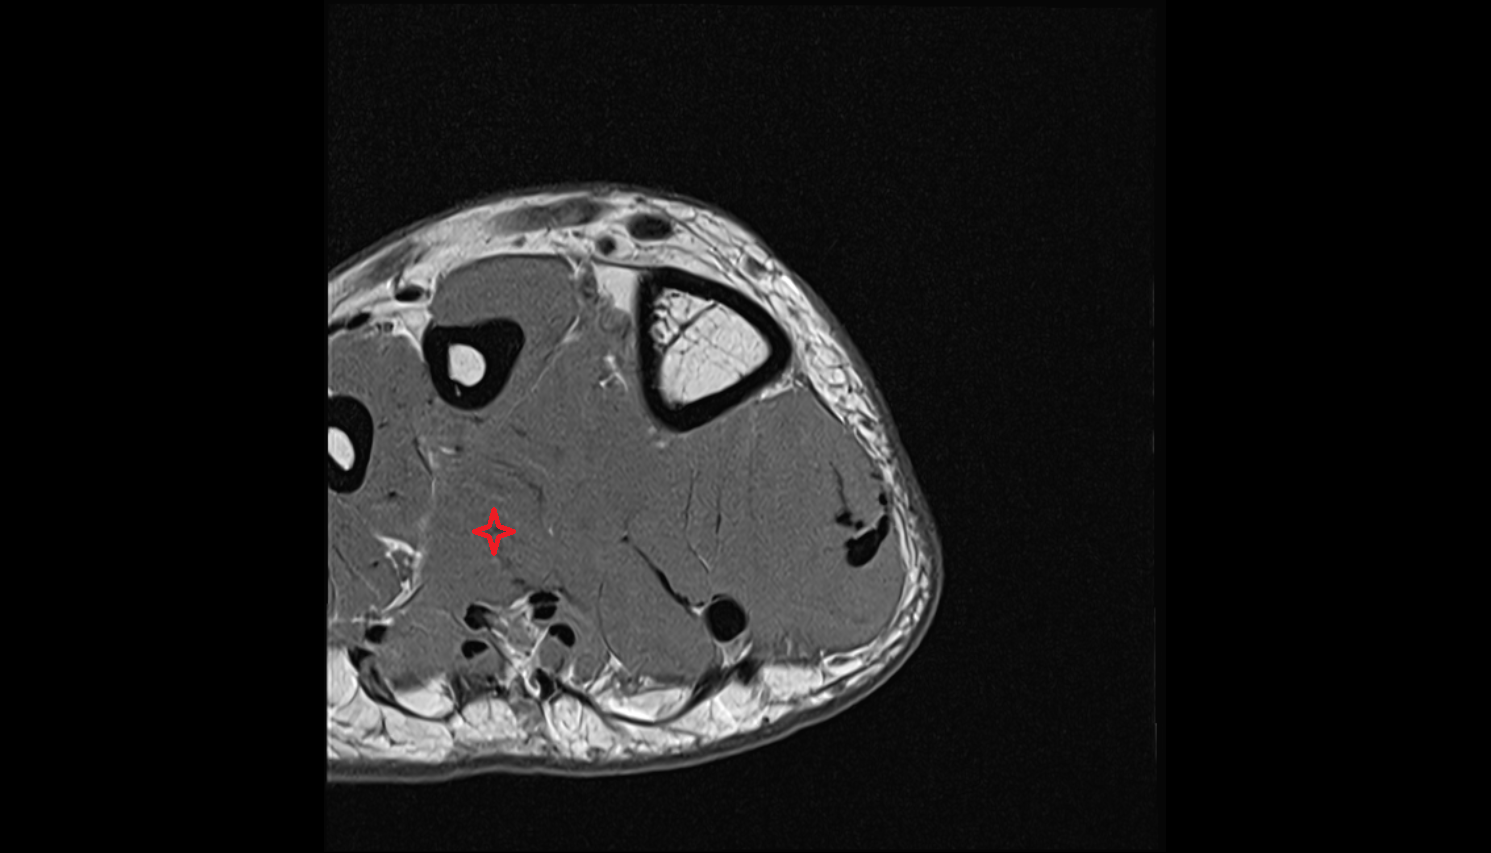

- Plantar aponeurosis